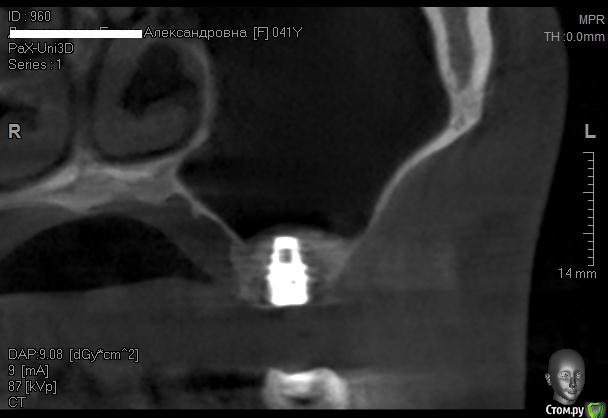

Kostoprav Опубликовано 12 июня, 2014 Автор Поделиться Опубликовано 12 июня, 2014 одновременно поставить -высоты кости не хватило ? 1-2 мм , я рисковать не захотел. 2 Ссылка на комментарий

Kostoprav Опубликовано 30 мая, 2015 Автор Поделиться Опубликовано 30 мая, 2015 все работает, чистая синтетика без ауто! это не единичный случай. 2 Ссылка на комментарий

Kostoprav Опубликовано 31 мая, 2015 Автор Поделиться Опубликовано 31 мая, 2015 а что за система имплантатов? noris Израиль Ссылка на комментарий